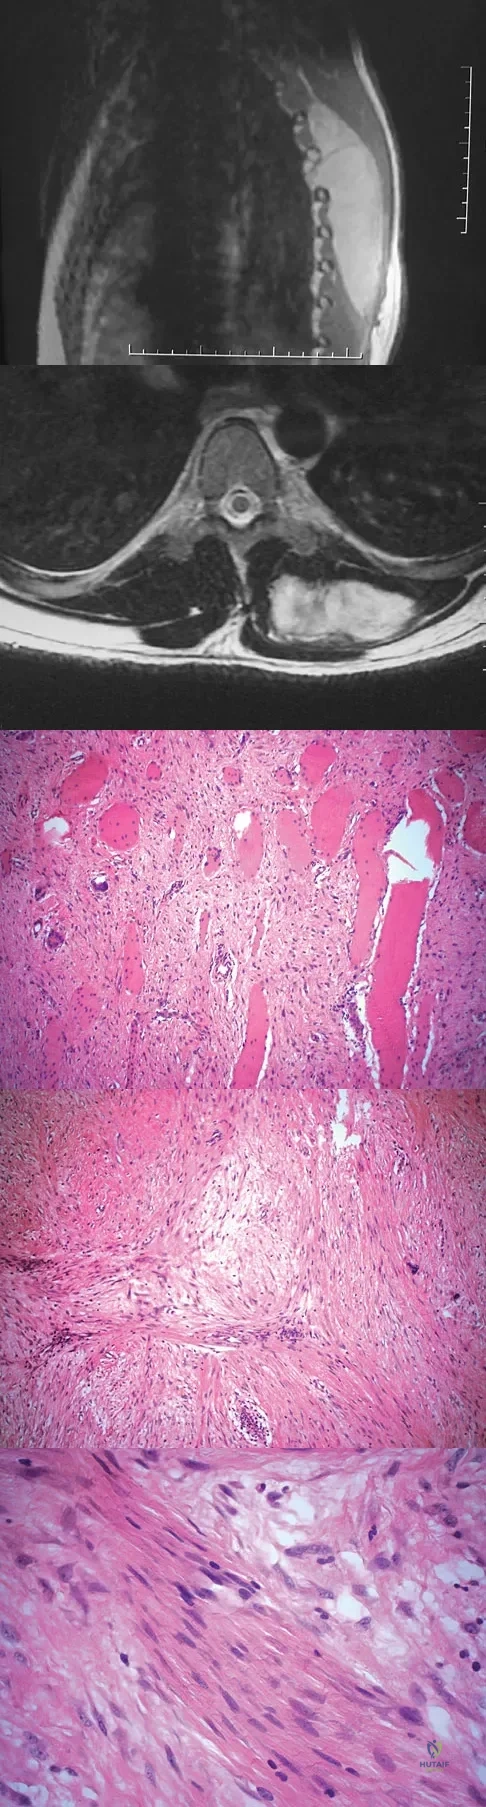

A 64-year-old man has had increasing pain in the left hip for the past 6 months. A radiograph and MRI scan are shown in Figures 25a and 25b. Biopsy specimens are shown in Figures 25c and 25d. What is the recommended treatment?

Explanation